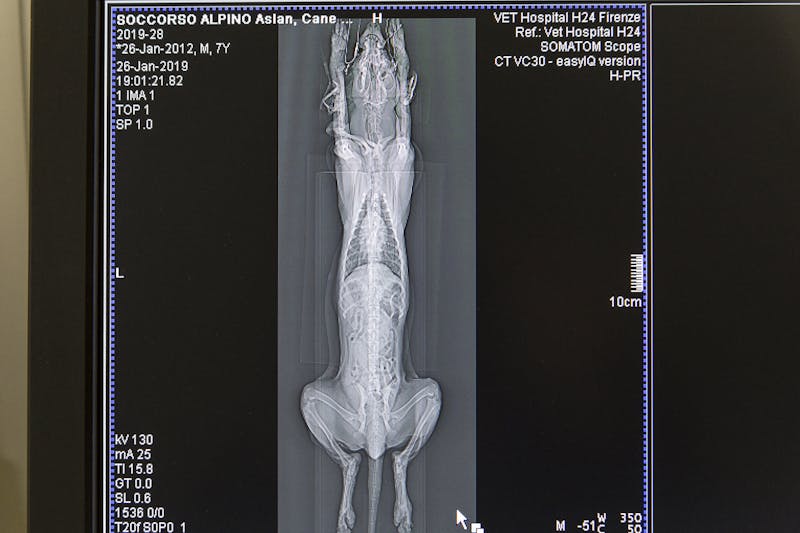

Così come successo in medicina umana, anche in quella veterinaria, la Diagnostica per Immagini è diventata una branca indispensabile della medicina. Per questo motivo, presso il nostro Ospedale abbiamo allestito un reparto specialistico di Diagnostica per Immagini che offre una vasta gamma di servizi di elevato standard qualitativo nei settori di Radiologia Digitale Diretta, Ecografia ed Ecocardiografia, Tomografia Computerizzata Multidetettore con e senza mezzo di contrasto. Il Vet Hospital H24 si avvale della collaborazione di uno staff costituito da medici specialisti nel settore della “diagnostica per immagini” e grazie all'utilizzo di attrezzatura di ultima generazione, propone esami diagnostici rivolti a tutti gli animali da compagnia convenzionali e non convenzionali.